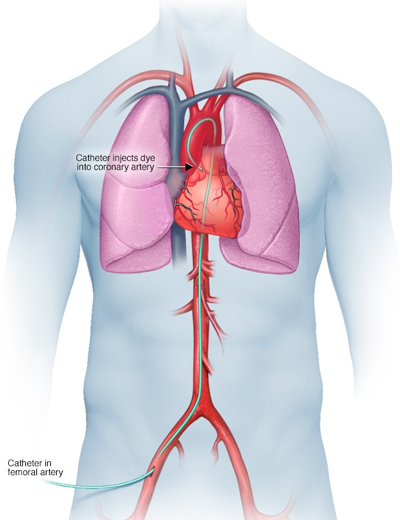

Coronary Angiogram

Angiogram is the gold standard for diagnosis of heart disease due to block. An easily detectable dye is injected into the artery through a catheter.